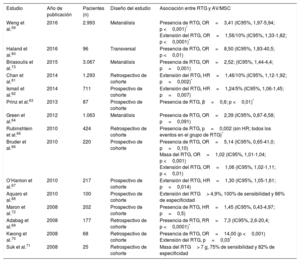

Estudios que informan del riesgo de arritmias ventriculares y muerte súbita cardiaca asociado con el RTG en pacientes con miocardiopatía hipertrófica

| Estudio | Año de publicación | Pacientes (n) | Diseño del estudio | Asociación entre RTG y AV/MSC |

|---|---|---|---|---|

| Weng et al.59 | 2016 | 2.993 | Metanálisis | Presencia de RTG, OR=3,41 (IC95%, 1,97-5,94; p <0,001)* Extensión del RTG, OR=1,56/10% (IC95%, 1,33-1,82; p <0,0001)* |

| Haland et al.60 | 2016 | 96 | Transversal | Presencia de RTG, OR=8,50 (IC95%, 1,83-40,5; p <0,01) |

| Briasoulis et al.73 | 2015 | 3.067 | Metanálisis | Presencia de RTG, OR=2,52; (IC95%, 1,44-4,4; p=0,001) |

| Chan et al.61 | 2014 | 1.293 | Retrospectivo de cohorte | Extensión del RTG, HR=1,46/10% (IC95%, 1,12-1,92; p=0,002)* |

| Ismail et al.62 | 2014 | 711 | Prospectivo de cohorte | Extensión del RTG, HR=1,24/5% (IC95%, 1,06-1,45; p=0,007) |

| Prinz et al.63 | 2013 | 87 | Prospectivo de cohorte | Presencia de RTG, β=0,6; p <0,01)* |

| Green et al.64 | 2012 | 1.063 | Metanálisis | Presencia de RTG, OR=2,39 (IC95%, 0,87-6,58; p=0,091) |

| Rubinshtein et al.65 | 2010 | 424 | Retrospectivo de cohorte | Presencia de RTG, p=0,002 (sin HR; todos los eventos en el grupo de RTG)* |

| Bruder et al.66 | 2010 | 220 | Prospectivo de cohorte | Presencia de RTG, OR=5,14 (IC95%, 0,65-41,0; p=0,10) Masa del RTG, OR=1,02 (IC95%, 1,01-1,04; p <0,001) Extensión del RTG, OR=1,06 (IC95%, 1,02-1,11; p <0,01) |

| O’Hanlon et al.67 | 2010 | 217 | Prospectivo de cohorte | Extensión del RTG, HR=1,30 (IC95%, 1,05-1,61; p=0,014) |

| Aquaro et al.68 | 2010 | 100 | Prospectivo de cohorte | Extensión del RTG> 4,9%, 100% de sensibilidad y 86% de especificidad |

| Maron et al.72 | 2008 | 202 | Prospectivo de cohorte | Presencia de RTG, HR=1,45 (IC95%, 0,43-4,97; p=0,5) |

| Adabag et al.69 | 2008 | 177 | Retrospectivo de cohorte | Presencia de RTG, RR=7,3 (IC95%, 2,6-20,4; p <0,0001)* |

| Kwong et al.70 | 2008 | 68 | Retrospectivo de cohorte | Presencia de RTG, OR=14,00 (p <0,001) Extensión del RTG, p=0,03* |

| Suk et al.71 | 2008 | 25 | Retrospectivo de cohorte | Masa del RTG> 7 g, 75% de sensibilidad y 82% de especificidad |

AV: arritmias ventriculares; HR: hazard ratio; IC95%: intervalo de confianza del 95%; MSC: muerte súbita cardiaca; OR: odds ratio; RR: riesgo relativo; RTG: realce tardío de gadolinio.